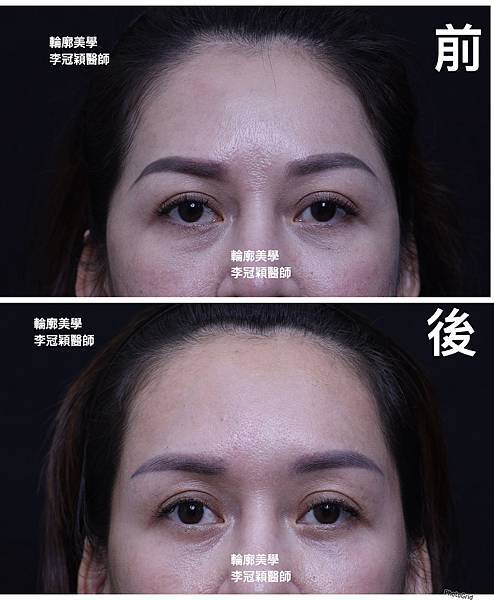

範例:先天臉型不對稱,經太陽穴墊片手術改善。

太陽穴墊片精準跳調整眉尾角度,改善下垂老態感。同時調整過窄的額型(尖頭型)

可以調節眉尾舒展角度和長度👍

下圖案例:太陽穴墊片精準調整眉尾角度提升,延伸眉尾長度改善下垂老態。

太陽穴墊片調整眉型和眼尾下垂,加強提眉效果和持久度。